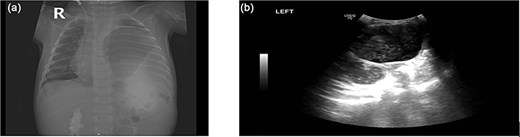

Chest radiograph showed an opaque left hemithorax with mediastinal shift to the right and a large air-fluid level, raising suspicion for diaphragmatic hernia with gastric herniation (Fig. 1a). Abdominal ultrasound revealed a cystic structure in the left thorax consistent with the stomach (Fig. 1b). Computed tomography confirmed a left posterolateral diaphragmatic defect with herniation of the stomach into the thorax, consistent with Bochdalek hernia and tension gastrothorax (Fig. 2).

(a) Opacified left hemithorax with shifting of the mediastinum to the right side due to possible left diaphragmatic hernia also there is right perihilar infiltrate. (b) US showed: Large cystic structure noted in the left side of chest likely stomach, diaphragmatic hernia cannot be ruled out.